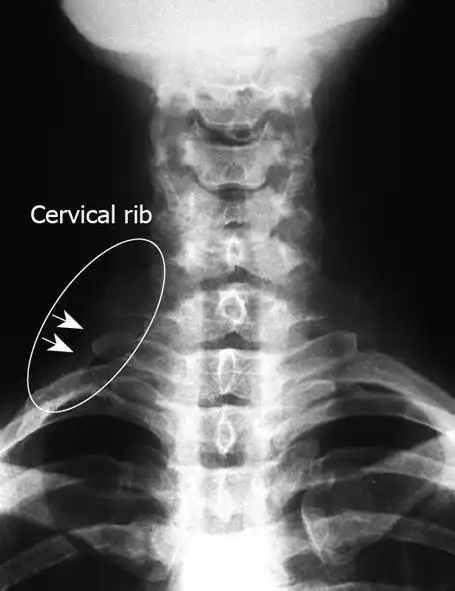

颈肋畸形